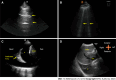

Acute decompensated heart failure entails a dysregulation of renal and cardiac function, with fluid volume excess or congestion being a key component. We provide an overview of methods for its assessment in clinical practice. Evaluation of congestion can be achieved using different methods including plasma biomarkers, measurement of blood volume from the volume of distribution of [131I]-human serum albumin, sonographic modalities, implantable devices, invasive measurements of volume status including right heart catheterization, and impedance methods. Integration into clinical practice of accessible, cost-effective, and evidence-based modalities for volume assessment will be pivotal in the management of acute decompensated heart failure.